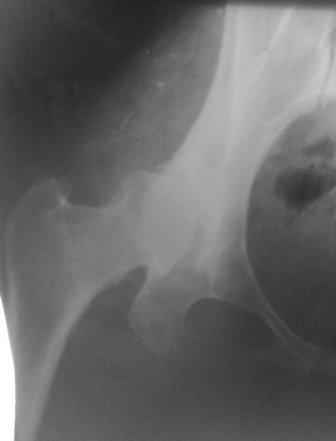

При определении показаний к м/в остеотомии учитываем не только функциональное состояние, но анатомическую форму сустава. Например, при той форме, что на картинке в вашем письме (мелкая впадина,уже не сферичная головка)НИИТО вполне обосновано предлагает ТЭП. Варизирующая остеотомия в "чистом виде" усилит конфликт в опорной зоне сустава. Если очень "настоятельно просит" - экстензия с наружной ротацией по R.Bombelli. То есть на открытом суставе бедро согнуть и ротировать внутрь до покрытия головки впадиной. Сформировать канал через шейку в головку с тем расчетом, что после м/в распила бедро нужно вывести в функциональное положение. Фиксировать 90 град. медиализирующей ортопедической пластиной с клинком. Но выздоровления не обещать, покрытие головки малое, длительного эффекта не будет. Нужна периацетабулярная остеотомия или пластика крыши, но это другая сложность и другая травматичность. Необходимость ТЭП оттянете лет на 10 в лучшем случае. Надо учитывать, что в этом случае ТЭП операция не первая, это увеличивает инфекц. риски и снижает функциональный результат для сустава. Я бы рекомендовал трость с противоположной стороны, ЛФК на приведение, чтобы подрос оссификат крыши и сформировались оссификаты головки. При нормотрофическом типе поражения можно будет провести вальгизирующую остеотомию, эффект которой более длительный или больная за это время найдет возможности приобретения ЭП.

Данный сустав в начальной стадии разрушения, но все-таки я бы сделал обзорный таз и отдельные снимки сустава в 30 градусной абдукции и аддукции. Также снимки с внутренней и наружной ротацией для оценки состояния головки бедра.

Представляю Р-снимки: обзорная, с отведением и с приведением.

Глубокоуважаемый Абдурашид. Здесь нет снимка с отведением. Если Вы сами сходили в рентгенкабинет и лично отвели пораженную конечность максимально возможно, а также дали максимально возможную внутреннюю ротацию-это одно!!!! Значит у пациентки тяжелейшая приводящая контрактура тазобедренного сустава!! И необходимо разобраться-миогенная или артрогенная? Если же Вы просто назначили указанный снимок и доверили произвести укладку рентгентехнику-это другое!!! Одному богу известно, что она делала, ведь на р-снимке отведения нет!

Все предыдущие корреспонденты предлагают вам достаточно простую вещь-смоделировать предлагаемую Вами операцию (т.е. дать отведение и внутреннюю ротацию) и посмотреть, как изменятся соотношения в суставе. Не обижайтесь, но судя по представлению клинического случая угловые величины, характеризующие пространственные соотношения в тазобедренном суставе, ваши рентгенологи не считают.

Уважаемый Игорь Владимирович. диссертации М М Камоска, и В Е Баскова я нашел, но почему-то не могу открывать, и еще в данном случае имеется дисплазия т/б за счет недоразвития крыши в/впадины да и всей подвздошной кости, маргинального вывиха или латеропозиции головки вследствие лечебных ощибок нет, головка стоит на месте. Р-граммы сделал сам, но почему-то у больной отведение и внутренная ротация стали очень болезненной, и сухожилия приводящих мышц сильно натягивается.(контрактура артро-миогенная).

Глубокоуважаемый Игорь Владимирович! Признаюсь допустил ошибку, из-за напряженности работы и нехватки времени, когда повторно внимательно посмотрел все понял и не успел исправить ошибку до Вашего поста, конечно скошенность крыши в пределах 40гр,часть головки кнаружи линии Омбредана-Перкинса , облитерация дна вертлужной впадины и т.д.-это ДМВБ.